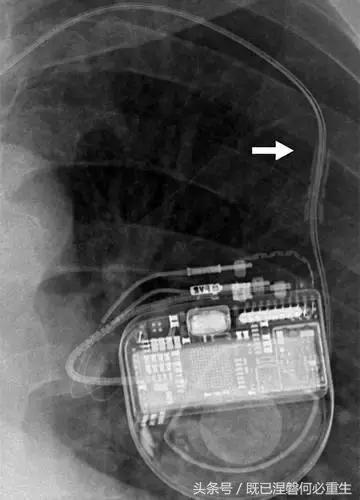

图。 7A 79岁的男性患有电极折断和迁移。

A,初始胸前X线片显示Pacesetter双腔起搏器低于锁骨的心房导线不完全断裂(变薄)(箭头)。

图。 7B 79岁的男性患有电极折断和迁移。

B,大约3年后,电极完全断裂,金属传导碎片(箭头)分离。 远端片段(箭头)已经偏移尾侧,但是由于围绕电极的射线可穿透鞘的束缚效应而没有迁移到肺循环中。 引线和中心静脉导管最常见于锁骨和第一肋骨之间断裂,因为它们在臂运动期间被锁骨下肌肉或腱或肋锁韧带压缩[16]。

造成设备故障的最常见的X光检查原因之一是铅断裂。锁骨下静脉经过锁骨下的部位是骨折最常见的位置[16](图7A和7B)。在这个位置的损伤可能发生在导管或导线,并已被描述为锁骨下夹断综合征和锁骨下压溃综合征[16?18]。临床上,骨折的导线通常在患者中产生可以是连续的,间歇的或依赖于患者定位的症状。识别这些状况可能需要挑衅性的动作,例如等长臂锻炼,仰卧或侧向定位或Valsalva。设备检查将显示异常的起搏阻抗(如果绝缘破裂允许导体暴露则减小,如果导体断裂但绝缘完好则增加),感测错误和起搏捕获损失[12]。导线断裂或绝缘损坏可能导致感测或起搏异常。对心律失常的不适当的过感知或欠感应可能导致不适当的治疗,例如抗心动过速起搏和休克治疗,或不适当的抑制治疗。